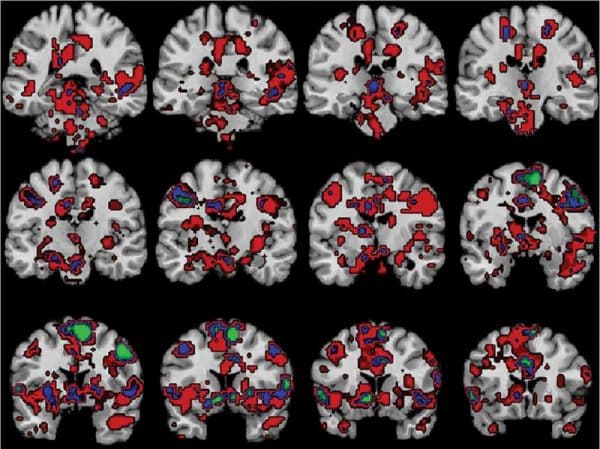

Comme la drogue, le sexe, la musique, la nourriture ou encore les jeux d’argent, les sentiments religieux activent les zones cérébrales impliquées dans le circuit de la récompense. C’est ce qui ressort d’une étude menée par l’université de l’Utah aux Etats-Unis et publiée dans la revue Social Neuroscience.